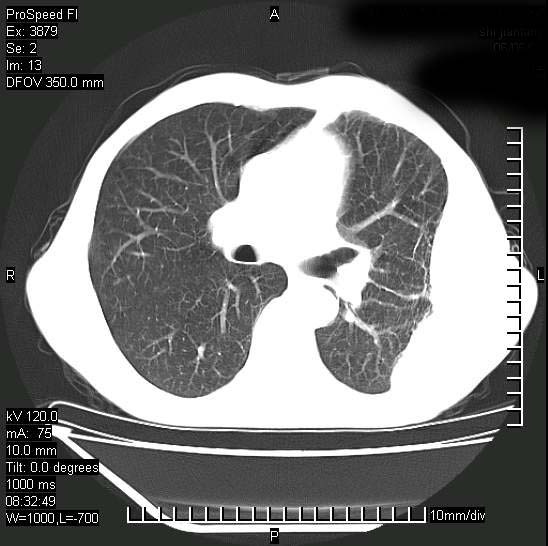

以下是引用37度在2008-6-6 11:20:00的发言:[br]1.包裹性积液,多考虑结核性;[br]2.穿刺术后改变。

以下是引用312nanyang在2008-6-6 15:12:00的发言:[br]基本支持楼主意见[br]疑问?左下肺支气管旁的软组织(16层)密度怎么解释?淋巴结还是斜裂胸膜增厚所致?能否增强进一步检查